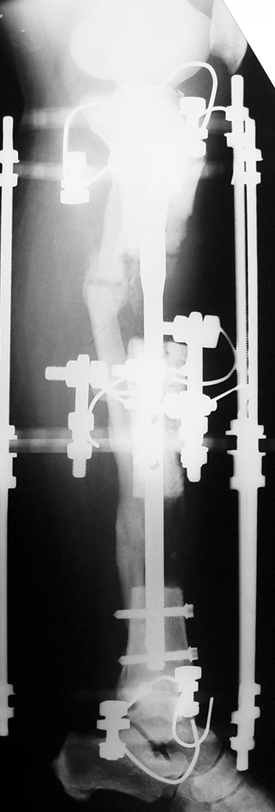

Appropriate radical debridement necessitates excision of all necrotic bone and soft tissues, and frequently causes instability at the involved extremity. The remaining bone and soft tissue defect has to be fixed and reconstructed. The distraction osteogenesis method of Ilizarov is used successfully for achievement of union, correction of the deformity, elimination of limb length inequality and reconstruction of segmental bone defects.

The duration of external fixation (external fixation index) depends on the amount of distraction required, and the extremity is prone to complications during this period. After the distraction phase is completed, the external fixator remains in place during the consolidation phase, which lasts twice as long as the distraction phase; but this period is hardly tolerated. If the external fixator is removed before sufficient consolidation is achieved, fractures, deformity and shortness will be the result. In our department, ‘lenghthening over nail’ method is used in order to decrease the external fixation index and increase patient comfort and activity level. In this method, the intramedullary nail is statically locked after the completion of the distraction phase, and external fixator is removed. The extremity is stabilized by the intramedullary nail during consolidation phase. In this way, complications due to long external fixation index or early removal of the external fixator are avoided.